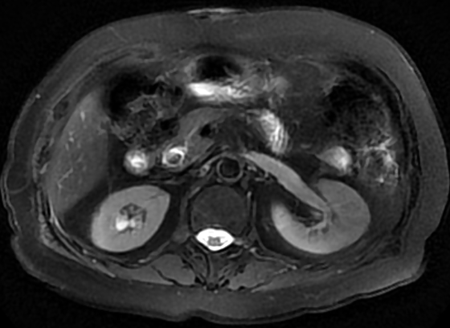

43岁的王先生是一名从事销售工作的职员,最近1个月反复“胃痛”,因为工作忙都是自己吃药对付。近3天发现小便像酱油一样,白眼球也有点发黄了,到医院检查发现胆管里面有一颗1cm大小的石头,胆囊也存在多发结石。我们给他做了腹腔镜下胆囊切除+胆管切开取石手术,术后很快尿色就正常了,肚子也没再疼。

胆管结石患者核磁检查提示胆管末端存在结石